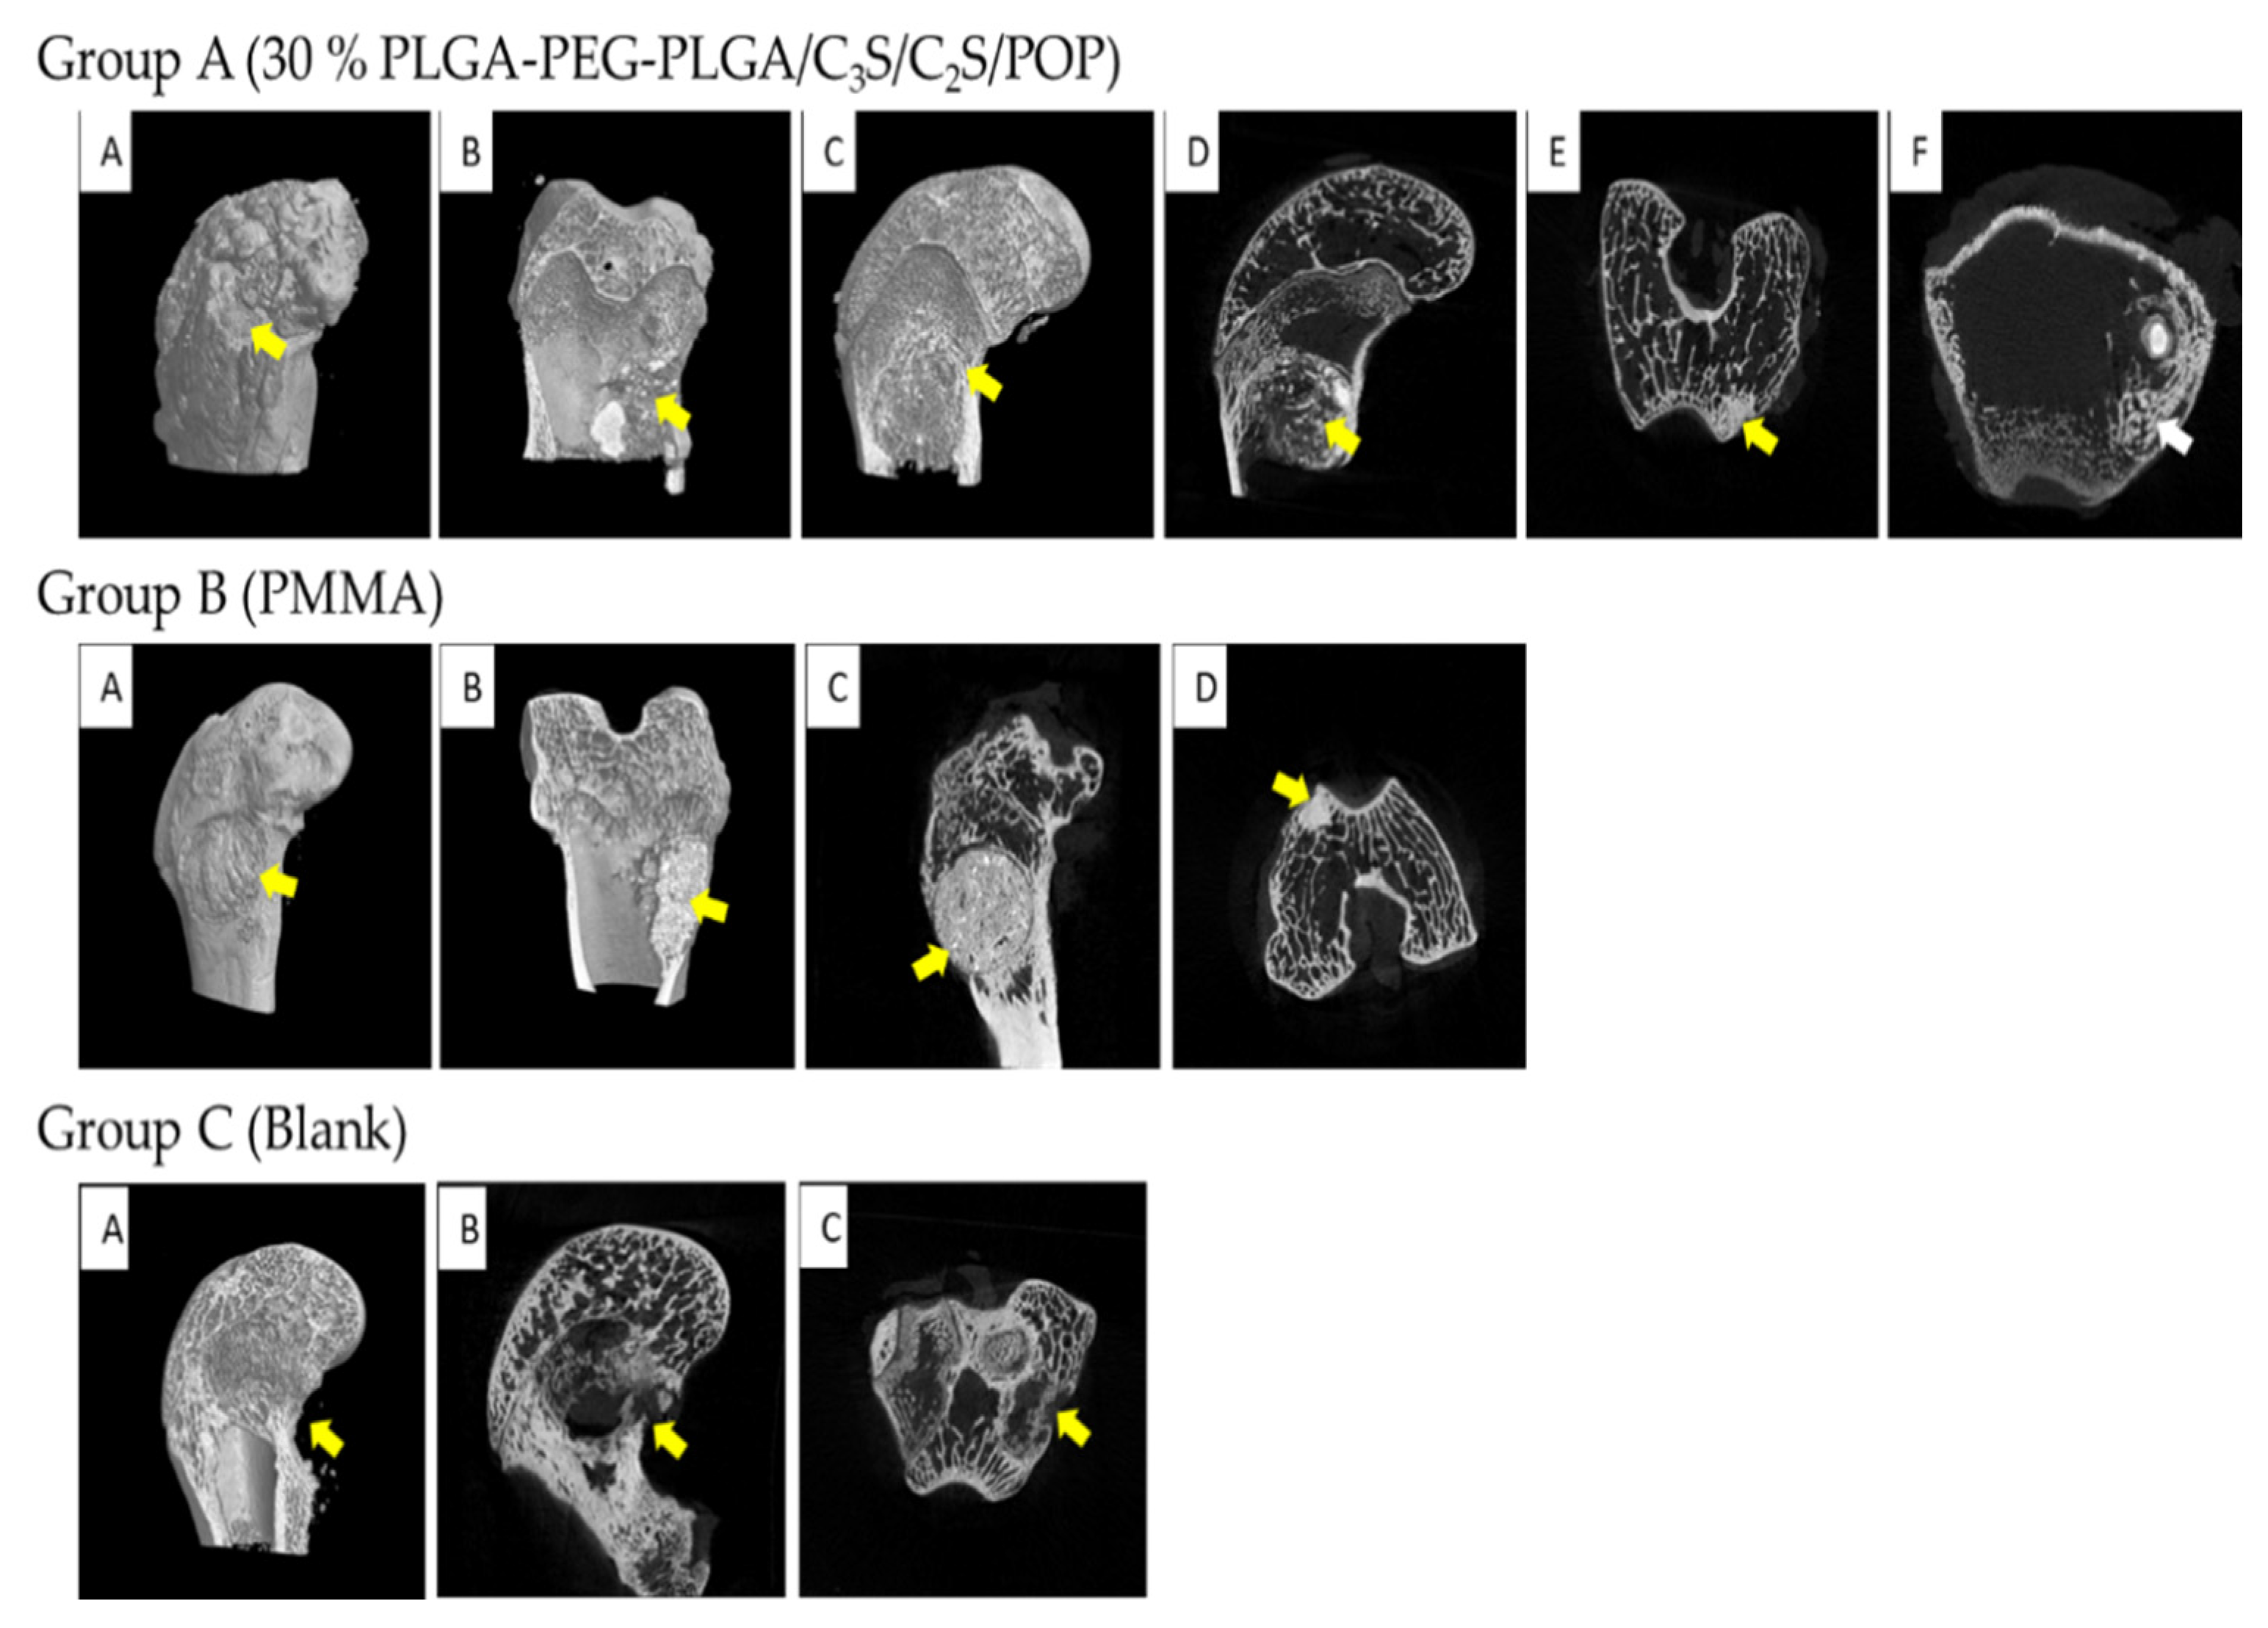

3.3. Animal Experiment